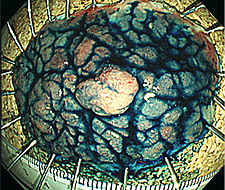

【早期食道がん】

NBI観察